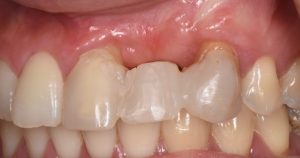

This video presents Part 2 of a staged pontic site development protocol, performed five months after the initial soft tissue augmentation. The objective of this second surgery is to further enhance soft tissue volume and achieve root coverage in preparation for a future fixed partial denture (FPD).

The procedure demonstrates the use of a horizontal vestibular incision with tunneling to mobilize the soft tissues and elevate the papillae. An autogenous connective tissue graft (CTG) harvested from the palate and maxillary tuberosity is utilized to augment tissue thickness. Additionally, a xenogenic bone graft is placed over the crestal area to serve as a space-maintaining scaffold and support vertical tissue stability.